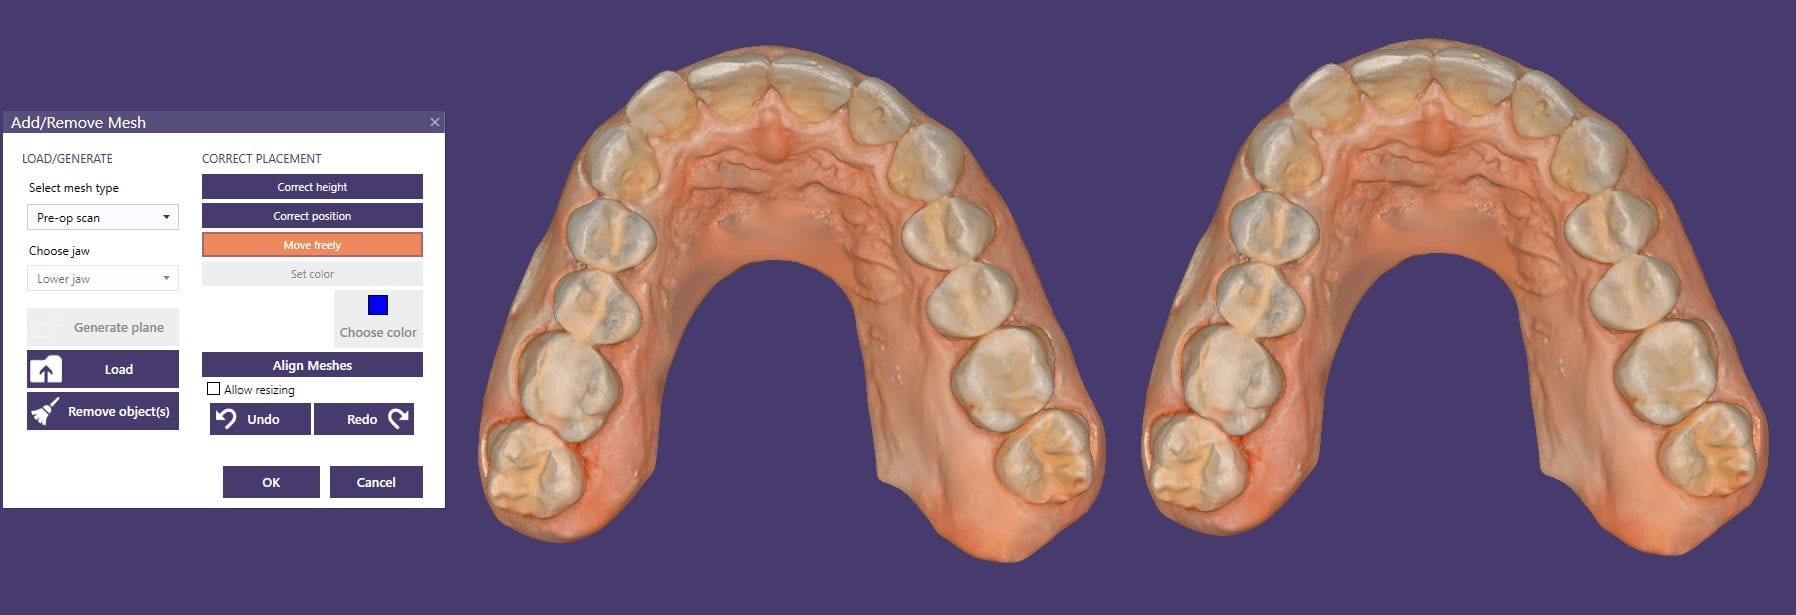

Meditlink Direct Link into CAD-Ray Software (powered by exocad) With Opportunity to Edit Job Definition And a Two Unit Copy Case Like You Have Never Seen Before!

May 21, 2019This case demonstrate some advanced features our CAD-Ray software provides for CAD/CAM users. We first launch meditlink and define the prescription. You can take your time and input your selection […]